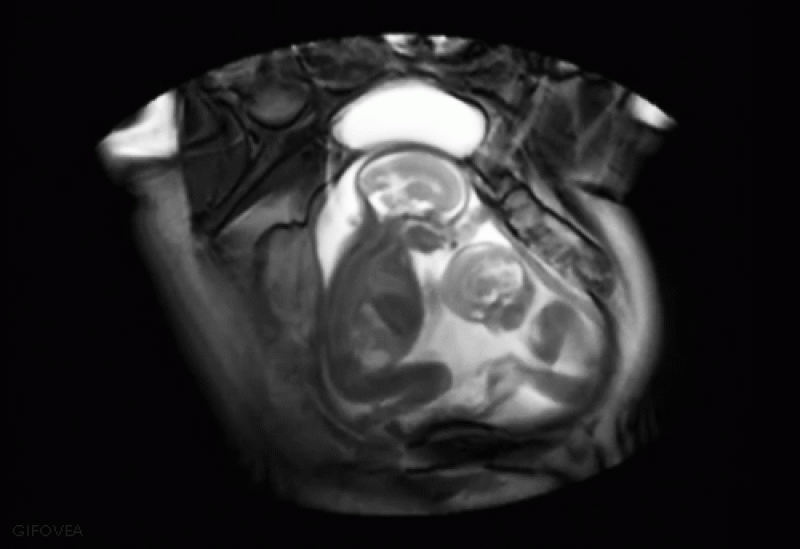

Tweelingen hebben al contact met elkaar in de baarmoeder.

De Universiteit van Padua ontdekte onlangs dat tweelingen al een nauwe band met elkaar hebben in de baarmoeder. Na 14 weken in de baarmoeder reiken de tweelingen al naar elkaar. Vier weken later raken de tweelingen elkaar al meer aan dan dat ze zichzelf aanraken.